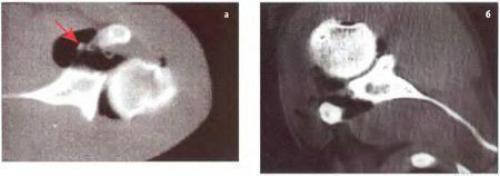

Рентгеноморфологическое изображение травматической нестабильности плечевого сустава на компьютерных томограммах (КТ) выглядит как отделение суставной губы с капсулой плечевого сустава от суставного отростка лопатки с заполнением этого дефекта рентгеноконтрастным кислородом.

На КТ в аксиальной проекции признаки повреждения Банкарта — отрыв суставной губы от переднего края суставного отростка лопатки (1)

На КТ в аксиальной проекции признаки костного повреждения Банкарта — отрыв суставной губы от переднего края суставного отростка лопатки с костным фрагментом

Таким образом, при компьютерной артропневмотомографии у всех пациентов с острой передней посттравматической нестабильностью плечевого сустава выявляют рентгенологические признаки классического повреждения Банкарта — отрыв суставной губы с капсулой плечевого сустава от передненижнего края суставного отростка лопатки и повреждения Хилла-Сакса — хондральный или компрессионный перелом головки плечевой кости.